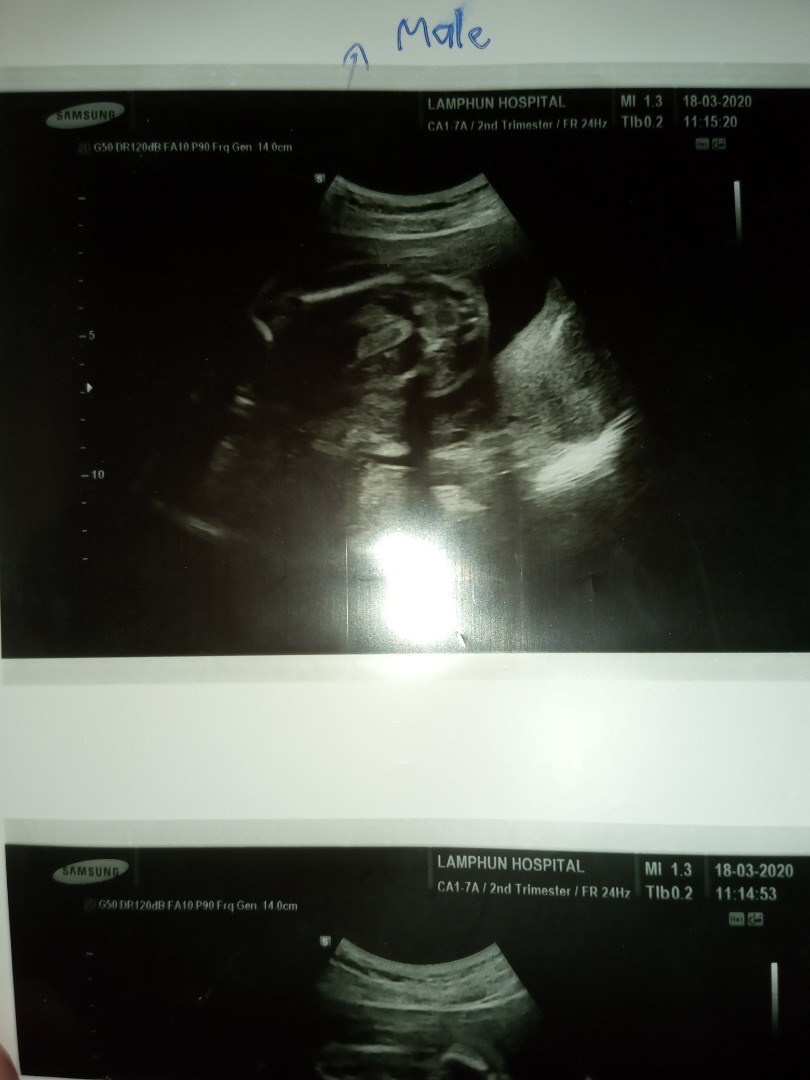

ใบซาวด์

ขอดูใบซาวด์เเม่ๆคลอดเดือนก.คหน่อยค่ะได้ผญหรือผชกันค่ะ

ชายจ้า 4 กค

ผช.แน่เลย